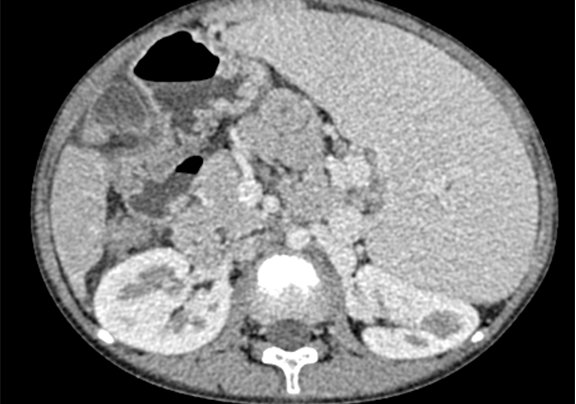

下腹部增强CT示:考虑肝硬化、脾大、门脉高压、侧枝循环形成、腹水可能性大。

术前CT检查:

动脉期

静脉期